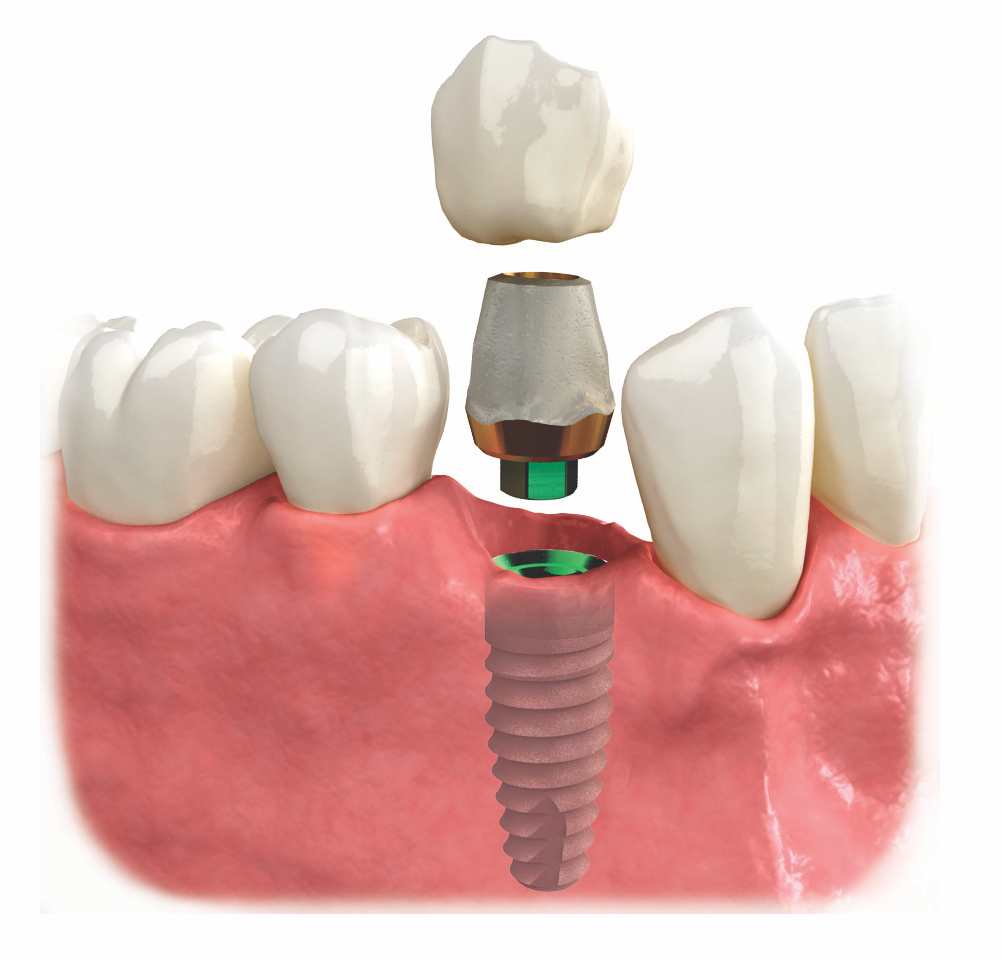

The implant acts as the “root” of your new tooth.

Once healing is complete, we attach the custom abutment and crown.

The crown is designed to perfectly match the shape and color of your natural teeth.

Our high-quality ceramic materials are both durable and lifelike.

The result: a tooth that looks, feels, and functions just like your own.